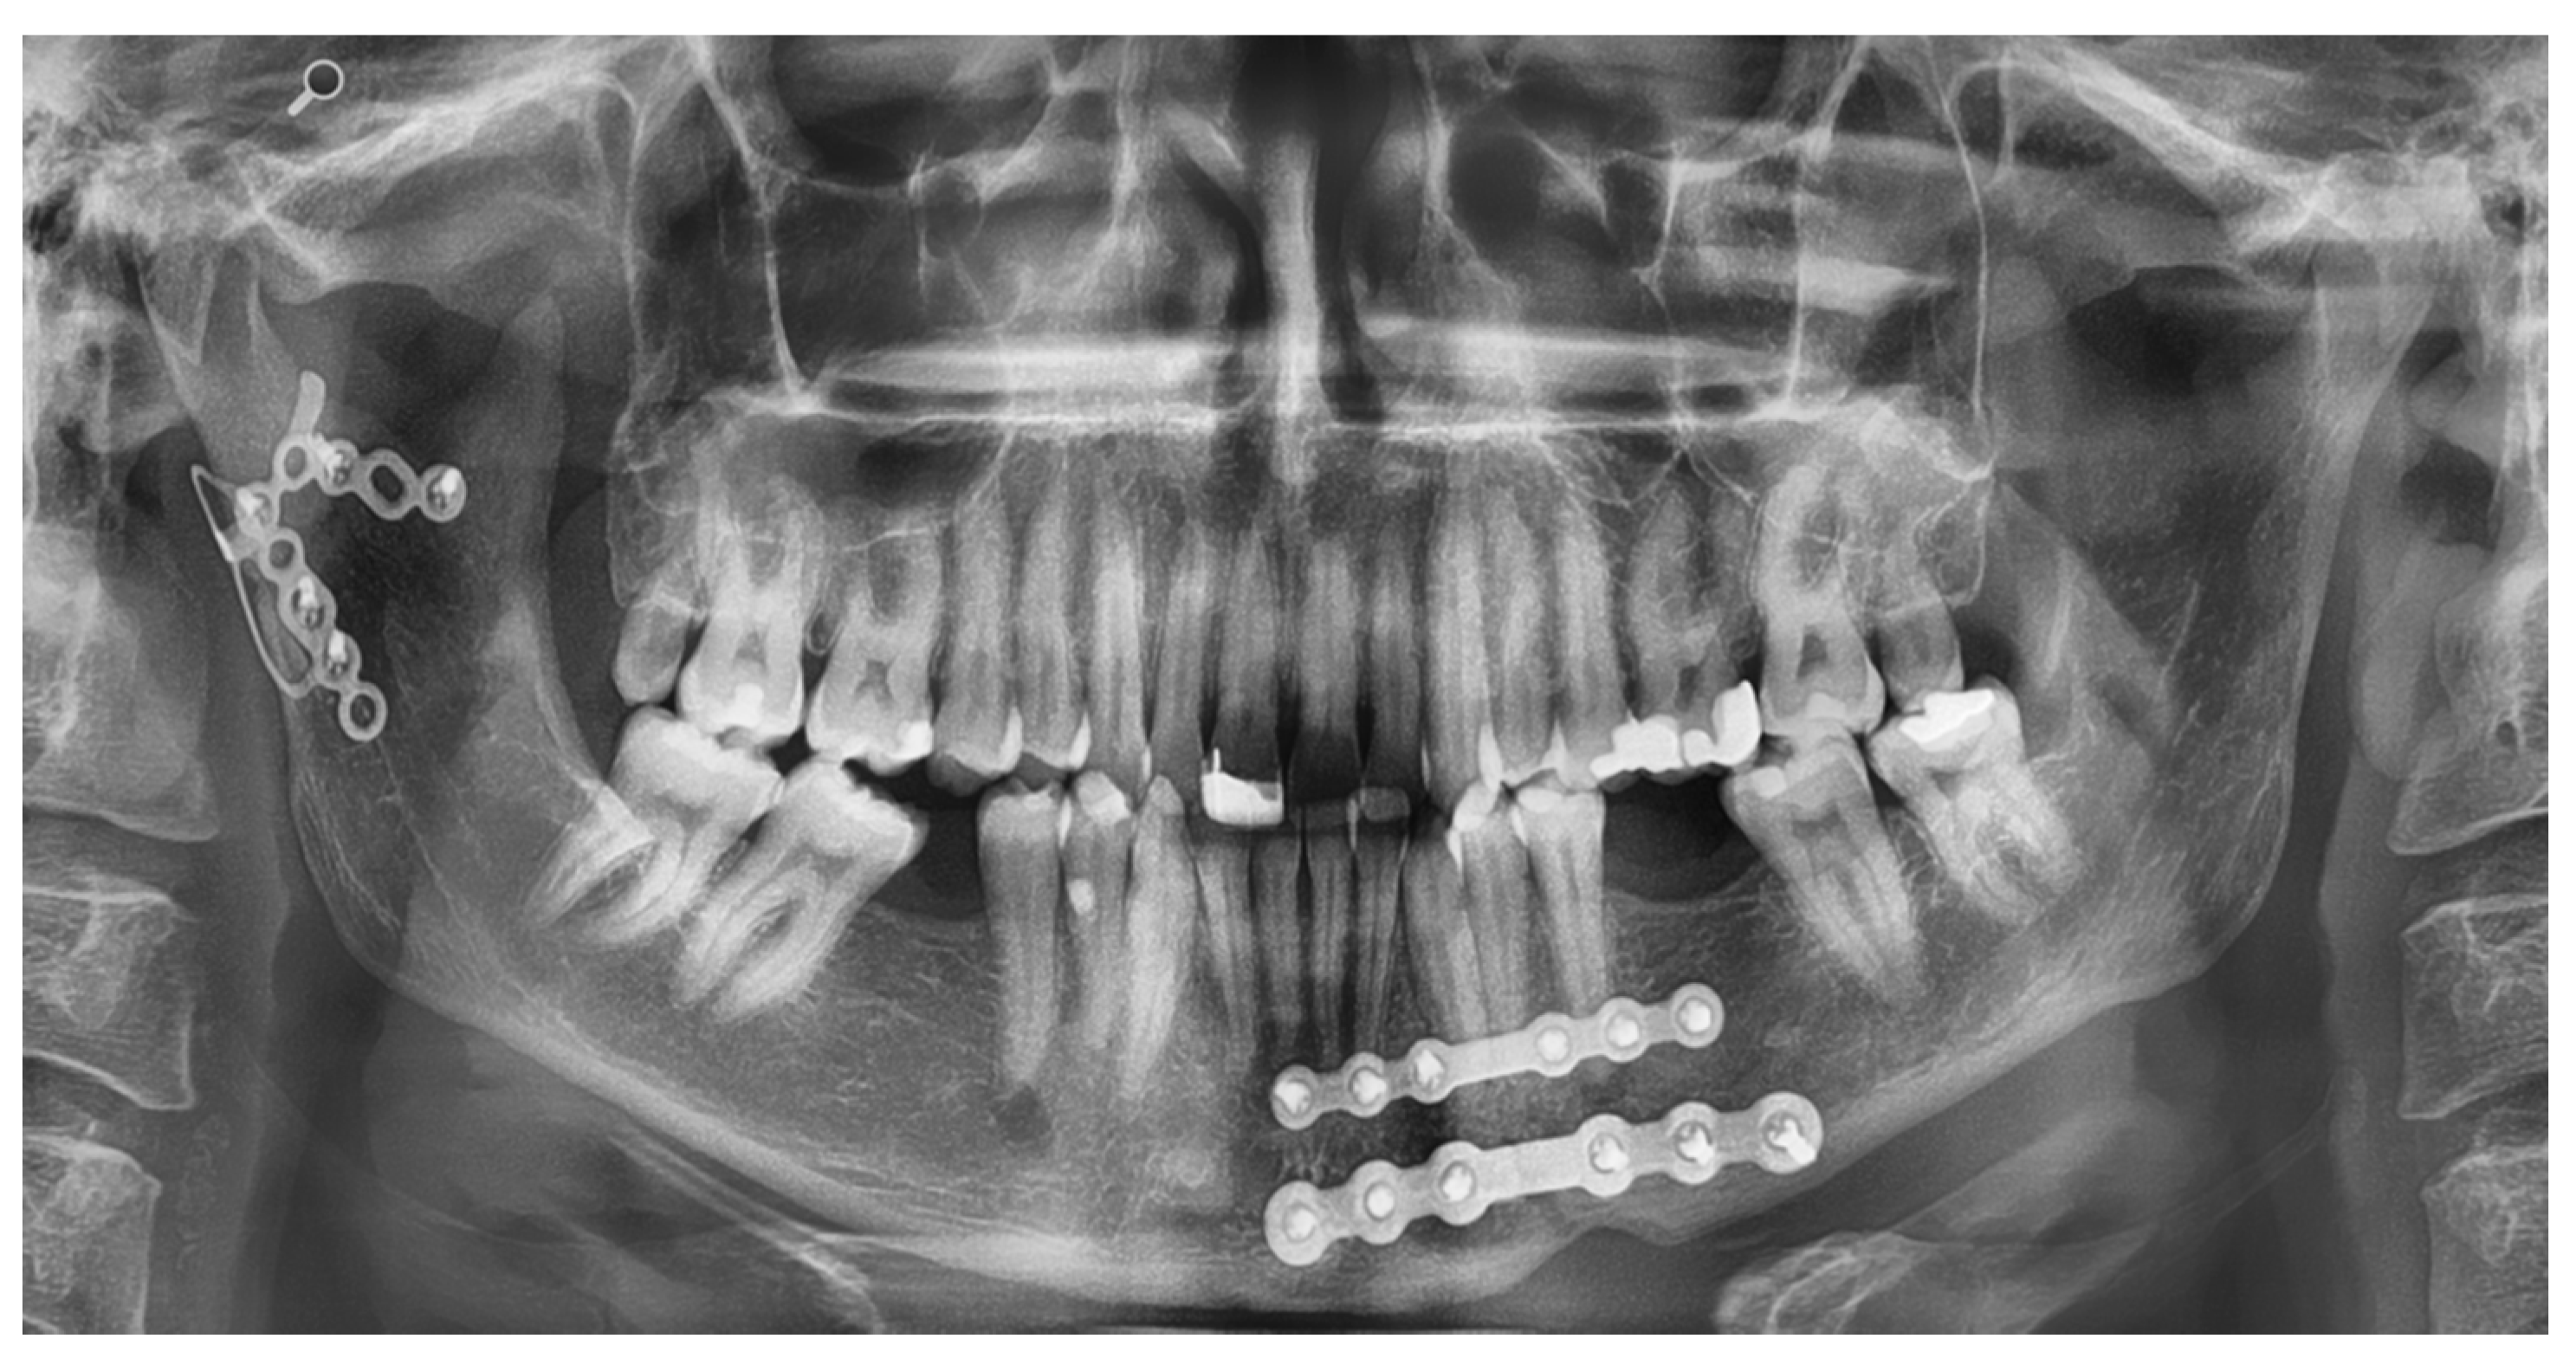

Application of the Plates

| Size L | Size M | Size S | Total | |

|---|---|---|---|---|

| Condyle plate | 74 | 85 | 75 | 78 |

| Body plate | 65 | 68 | 80 | 71 |

| Ramus plate | 47 | 60 | 53 | 53 |

| Symphysis plate | 84 | 90 | - | 87 |